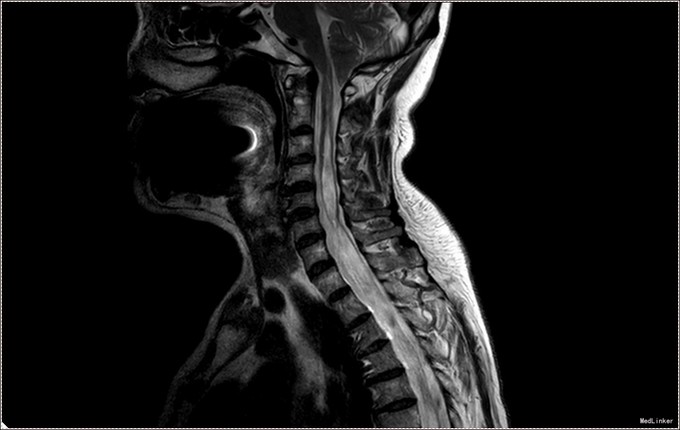

入院查体:神清语明,问答准确,查体合作,精神状态良好。双侧瞳孔等大正圆,D≈3.0mm,双侧眼球活动自如,对光反射灵敏。双下肢肌力减退,肌力三级,肌张力正常。双上肢肌力正常,活动自如。四肢感觉减退,可见多处烫伤瘢痕。双巴氏征(-)。 颈椎MR提示小脑扁桃体下疝畸形,脊髓空洞症(C1-T6);颈椎管狭窄,颈椎间盘膨出(C3-C6)

患者诊断明确,完善术前检查。行枕下减压,扩大修补硬膜,颈髓空洞穿刺。术后予常规治疗。复查颈椎MR提示小脑扁桃体减压充分,脊髓空洞略缓解。但术后3日起发热,行腰穿提示椎管内感染,行腰池引流1周,拔管出院。出院时患者自述左侧肢体麻木感减轻,双下肢肌力较入院好转。